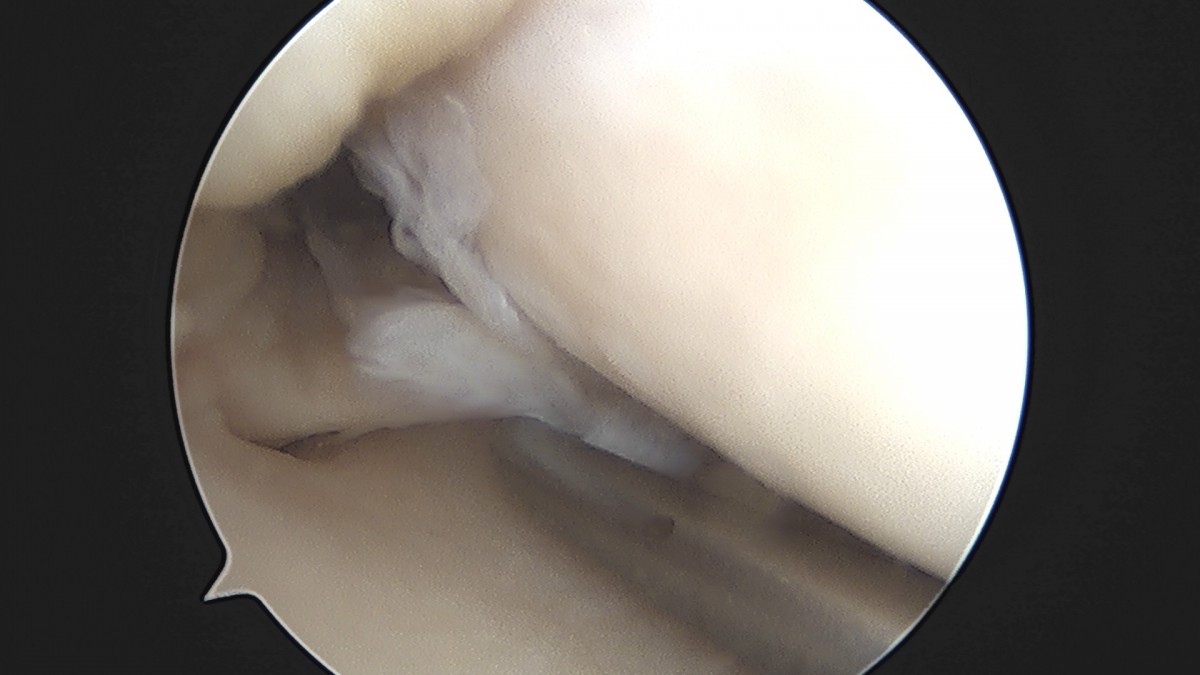

이재상원장님 무릎 반월상 연골판 절제술 고기O 환자

dae765e4d9ac96aee867c9d6292d8784_1758005091_6618.jpg